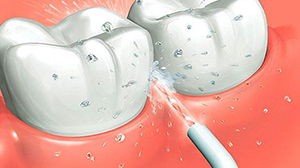

Применение ирригатора

Аппарат смывает налет, остатки еды из труднодоступных мест. Выполняет массаж десен, способствует улучшению кровообращения для более активного восстановления мягких тканей. Для лучшего эффекта в ирригатор можно заливать антисептические или лекарственные препараты.

Устройство незаменимо при уходе за несъемными мостовидными конструкциями на имплантатах. Направляя струю жидкости в межзубные пространства, удается очищать область импланто-десневого контакта. Продолжительность процедуры составляет 3-5 минут дважды за день.